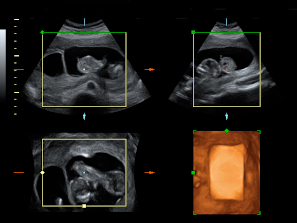

Ecografía Embarazo 2D y 3D Semana 12 - ANOMALIAS CROMOSÓMICAS